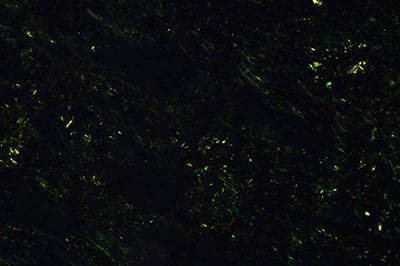

Olympus’ commitment to innovation produced the True Color LED (patent pending), which provides the color rendering and luminosity performance that pathologists are accustomed to with the halogen lamp and filter method. The high-quality illumination of this new light source is not achievable with commercially-available bright LEDs. The BX53 microscope equipped with this white LED light source is advantageous for transmission brightfield microscopy as well as other observation methods. Its brightness level is intense enough to be used in multiheaded discussion and teaching systems for simultaneous observation, and its high color rendering white LED provides the color integrity performance that pathologists require for reliable specimen observation.

Figure 6: Multiheaded discussion system (left) for 26 people and observation image (right)